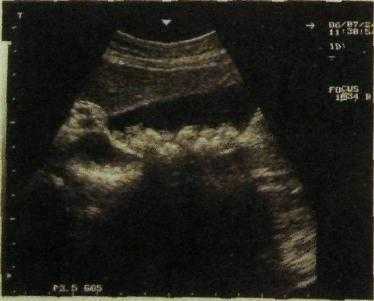

Гепатоцеллюлярный рак (гепатома) обусловливает на сонограммах участок неравномерной плотности с неровными контурами (рис. Ш.141). Распад опухоли выглядит как эхонегативная зона неправильной формы, а отек вокруг опухоли — как расплывчатый ободок, тоже эхонегативный. На компьютерных, магнитно-резонансных томограммах и сцинтиграммах (эмиссионных томограммах) гепатома обусловливает дефект неправильной формы с неровными очертаниями (рис. III. 142).

Рис. Ш.141. Сонограмма печени. Гепатоцеллюлярный рак. Опухоль сдавливает нижнюю полую вену и прорастает в воротную вену.

1 — передняя брюшная стенка; 2 — печень; 3 — ветвь воротной вены; 4 — гепато-ма; 5 — нижняя полая вена.